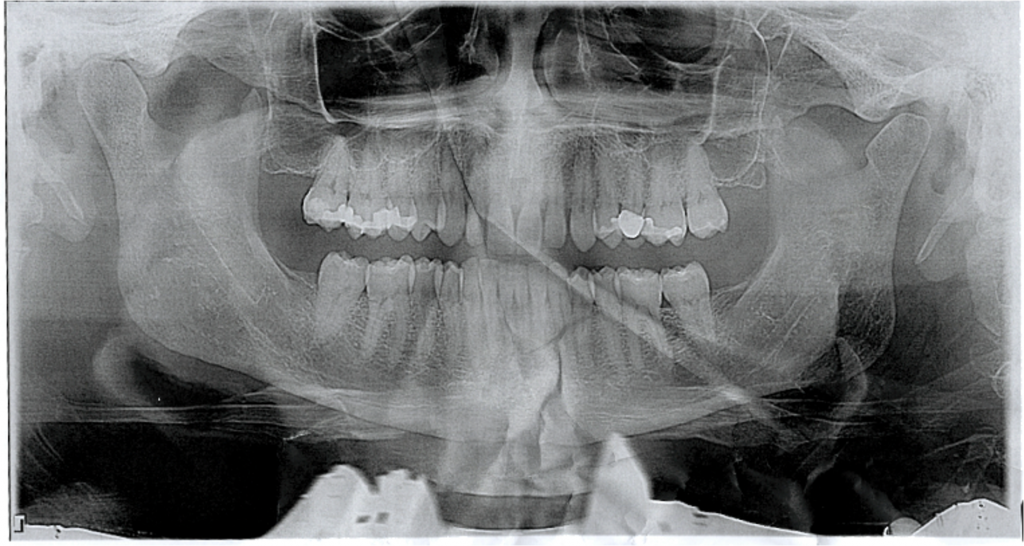

The big event for the day was going to the dentist.. I know it sounds crazy.. but I love going.. it feels good and I find it relaxing.

All looks good.. dont you think ?